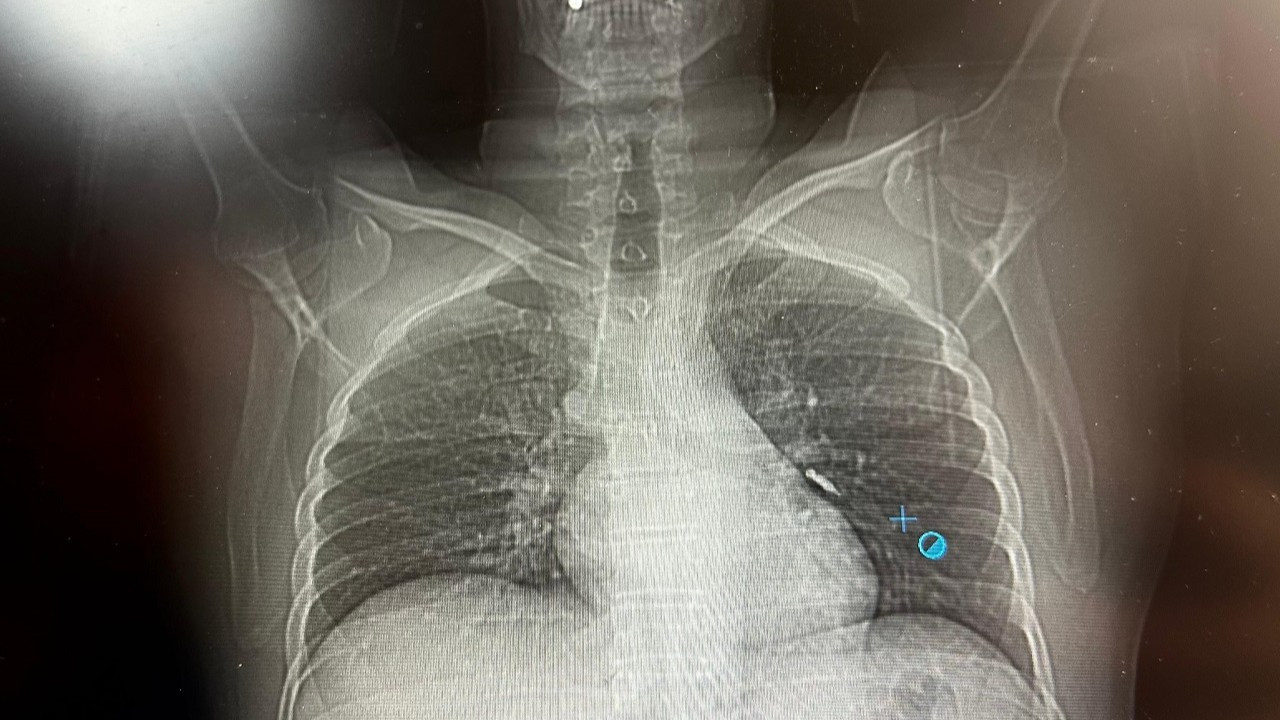

Daha sonra hasta için yeniden bronkoskopi planladıklarını ancak bu süreçte hastanın şiddetli bir öksürük geçirdiğini aktaran Aksoy, "Şiddetli öksürük sonrası yapılan kontrol akciğer filminde implant vidası görünmedi. Bunun üzerine toraks ve batın BT (bilgisayarlı tomografi) görüntülemesi istedik. Sonuçlarda implantın akciğerden çıktığı ve vücutta herhangi bir yerde bulunmadığı tespit edildi" dedi.